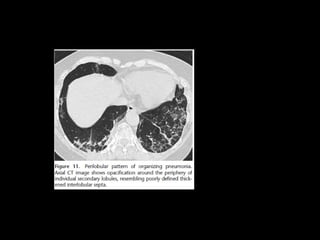

Aguda/subaguda COP • Ex BOOP •Asociada a : colágeno, infecciones, EII, radiación, toxicidad, transplante órganos Criptogénica: idiopática 55 h=m 4- 6 semanas con síntomas de gripe Buen pronóstico

COP histología • Tejidogranulación dentro de los ductos alveolares asociado a infiltrados mononucleares • pólipos

COP CT • Consolidacionesparcheadas • Broncograma aéreo Signo halo inverso • Vidrio esmerilado periférico o peribroncovascular • Crazy paving • LI • Nódulos, cavitarse • Puede simular neumonía • Reticulación subpleural • Derrame pleural

Bilateral or unilateralpatchy alveolar airspace consolidation is revealed, often subpleural and peribronchial in location and mainly in the lower zones. Generally, the infiltrates gradually enlarge from their original size or new infiltrates appear. Consolidation is often nonsegmental and varies from 2 to 6 cm in diameter. Cavitary BOOP that mimics tuberculosis and cavitating opacity after lung transplantation has been reported. An air bronchogram may be present. Nodules 3-5 mm in diameter are seen in approximately one half of patients; nodules may be migratory. Basal linear opacities are linked to a poorer prognosis. Unilateral focal or lobar consolidation occurs in 5-31% of patients. Miliary pattern is rare. Pleural thickening occurs but pleural effusions are rare.